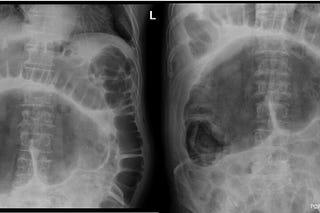

Cecal Volvulus

Jacob C Davis, DO